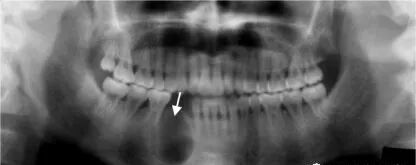

关节相关常见疾病:

颞下颌关节紊乱病 TMJD:

3)X 线:

(1)关节间隙改变:前大后小,前小后大,整体变窄,整体变宽;

(3)两侧关节形态发育不对称;

(4)骨质改变

关节

(1) 关节间隙改变:前大后小,前小后大,整体变窄,整体变宽;

(2) 两侧关节形态发育不对称;

(3) 骨质改变:(可追加薛氏位片或MRI)

正畸前拍摄全景片,检查患者牙体、牙髓、牙周、关节等情况,可以帮助正畸医生更好的把握患者正畸前情况,合理制定方案,对于全景片无法清晰显示的位置,可以再通过拍摄cbct或者单牙位片的方式进行诊断。原则是尽可能在正畸前完成全面的检查并记录,既是对患者负责,又是对我们方案、治疗过程的有效信息的掌握。避免纠纷和风险。你懂~~~~~